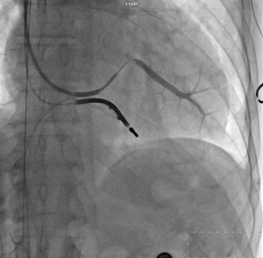

? CRT-D成功植入

?“它的技術難點在于左室電極的植入”。朱彬介紹,除了常規(guī)的由于心臟擴大變形所致的冠狀靜脈竇口位置改變,自身冠狀靜脈解剖異常等問題外,傳統(tǒng)的左室電極安置后存在起搏位點選擇性小,起搏時容易出現(xiàn)膈神經(jīng)或膈肌刺激、起搏高閾值、為保證穩(wěn)定性將電極植入心尖而出現(xiàn)心尖部起搏,為避免心尖部起搏避開心尖位置但卻出現(xiàn)電極不穩(wěn)定術后移位等諸多問題。而左室四極電極導線由于可以有多個起搏位點和多種起搏向量的選擇,可一次性解決上述難題,能做到“電極植入心尖,起搏心底”。綜合患者具體情況,為提高手術成功率,降低手術風險,朱彬決定在該手術中使用目前國內最新型的左室四極電極。